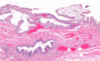

Shown here is the geographic pattern associated with Primary Sclerosing Cholangitis.

Large duct inflammation - acute, neutrophilic infiltration of the epithelium superimposed on a chronic inflammation

Smaller ducts, have little inflammation and show a striking circumferential “onion skin” fibrosis around an atrophic duct lumen, with eventual obliteration.